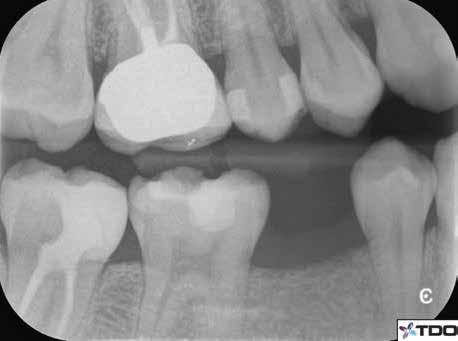

1. a-n. ábrák: Preoperatív CBCT-felvétel a bal alsó 6-os (3.6) fogról. Az axialis (a), coronalis (b) és sagittalis (c) nézeteken a mezialis és distalis gyökerek apicalis harmada körül sugáráteresztő zóna és ép buccalis corticalis csont látható. Egy olyan sablont terveztünk, amely jelezte a csontablak határait az apicalis terület pontos elérése érdekében (d). A mikrosebészeti bevatkozás során a sablont a helyére illesztettük (e), a csontablak határait megjelöltük (f) egy Piezotome CUBE LED kézi-darabba fogott fűrésszel, majd kivágtuk és eltávolítottuk (g és h) az apicalis területhez történő hozzáférés, illetve a mezialis és distalis gyökerek rezekciójának, retrográd preparációjának és retrográd gyökértömésének elvégzése érdekében (i). Végezetül a csontablakot visszaillesztettük és kollagén szivaccsal stabilizáltuk (j). A műtét után közvetlenül készített röntgenfelvétel a 3.6-os fogról (k). A kétéves kontroll során készített CBCT-felvétel: axialis (l), coronalis (m) és sagittalis (n) nézetek.

Egy 63 éves páciens korábban már kezelt bal alsó első nagyőrlőfogából (3.6) eredő mérsékelt fájdalom miatt kereste fel rendelőnket. A kórtörténetében panasza szempontjából releváns információ nem szerepelt. Az elkészült CBCT-felvételen a korábbi kezelések során észre nem vett, jelenleg feltáratlan meziobuccalis csatornát, valamint a mezialis és distalis gyökerek körül kialakult periapicalis elváltozást, és ezt a léziót borító intakt buccalis corticalis csontlemezt láttunk.

Klinikai vizsgálat során vertikális kopogtatási érzékenységet jelzett. A fog körül mérhető szondázási mélység és a fogmobilitás fiziológiás volt. A CBCT-felvételen nem észleltünk a csontos regeneráció megindulására utaló jeleket (1. a–c. ábrák). A korábban gyökérkezelt, gyökértömött és revideált 3.6-os fog esetében az alábbi diagnózis került felállításra: periodontitis periapicalis symptomatica. A panaszokat okozó fog további ellátása során navigált endodonciai mikrosebészetet kívántunk alkalmazni. Az alsó állcsontról intraorális szkent (TRIOS, 3Shape) készítettünk, és a felszíni topográfiát tartalmazó STL fájlt, valamint a CBCT-felvétel készítése során nyert DICOM fájlokat a Blue Sky Bio szoftver segítségével egyesítettük. A sebészi sablon megtervezésére az így kapott háromdimenziós képet használtuk. A sablon kialakítása során arra törekedtünk, hogy a sablon egyértelműen meghatározza a gyökércsúcsi terület eléréséhez szükséges csontablak határait (1. d. ábra)